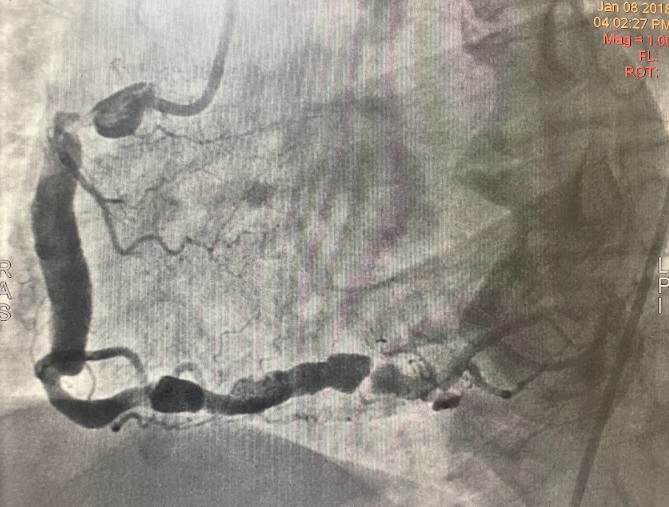

Coronary angiography showed a dominant RCA with a large proximal aneurysm measuring 4.5 ¡¿ 17 mm, with in-stent restenosis proximal to the aneurysm. Mid-to-distal RCA was ectatic. The LM, LAD, and LCx were also mildly ectatic but without significant stenoses. These findings were consistent with a giant RCA aneurysm, likely related to prior stent implantation.